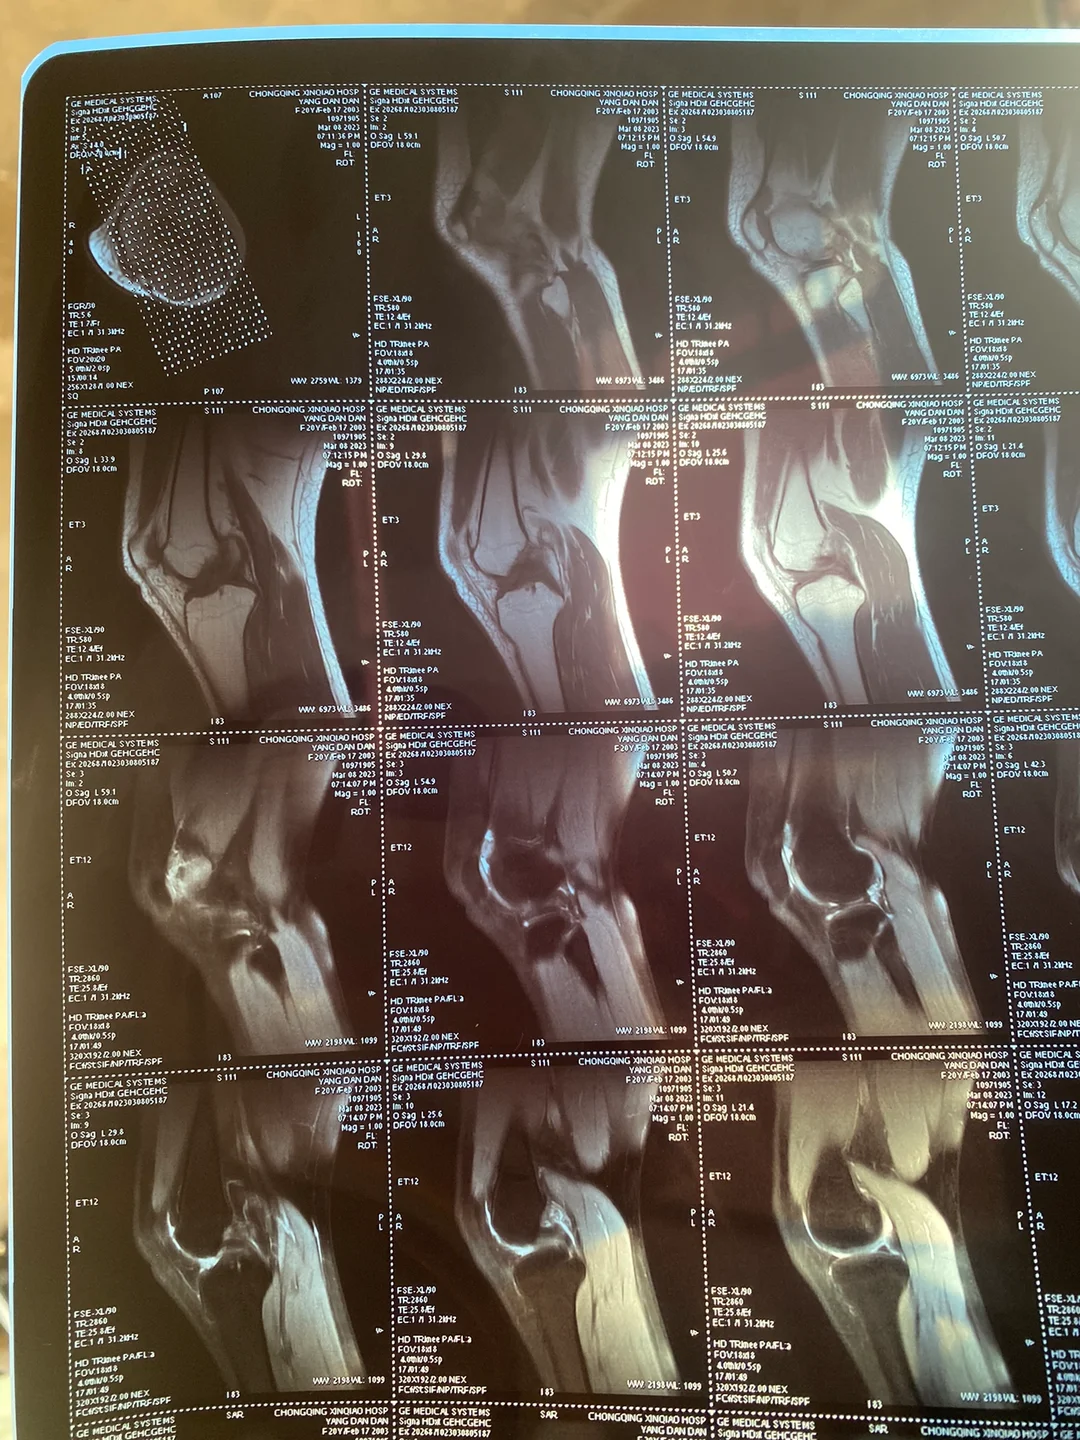

半月板后角撕裂MRI表现

1、半月板的退行性病变或撕裂在MRI上均可表现为半月板内的高信号影垂直撕裂多见于年轻人,MRI表现撕裂处信号强度增高,因关节内液体充满撕裂口处水平撕裂多见于老年人,MRI上呈高信号强度,是粘液样退行性变发生在半月板中...